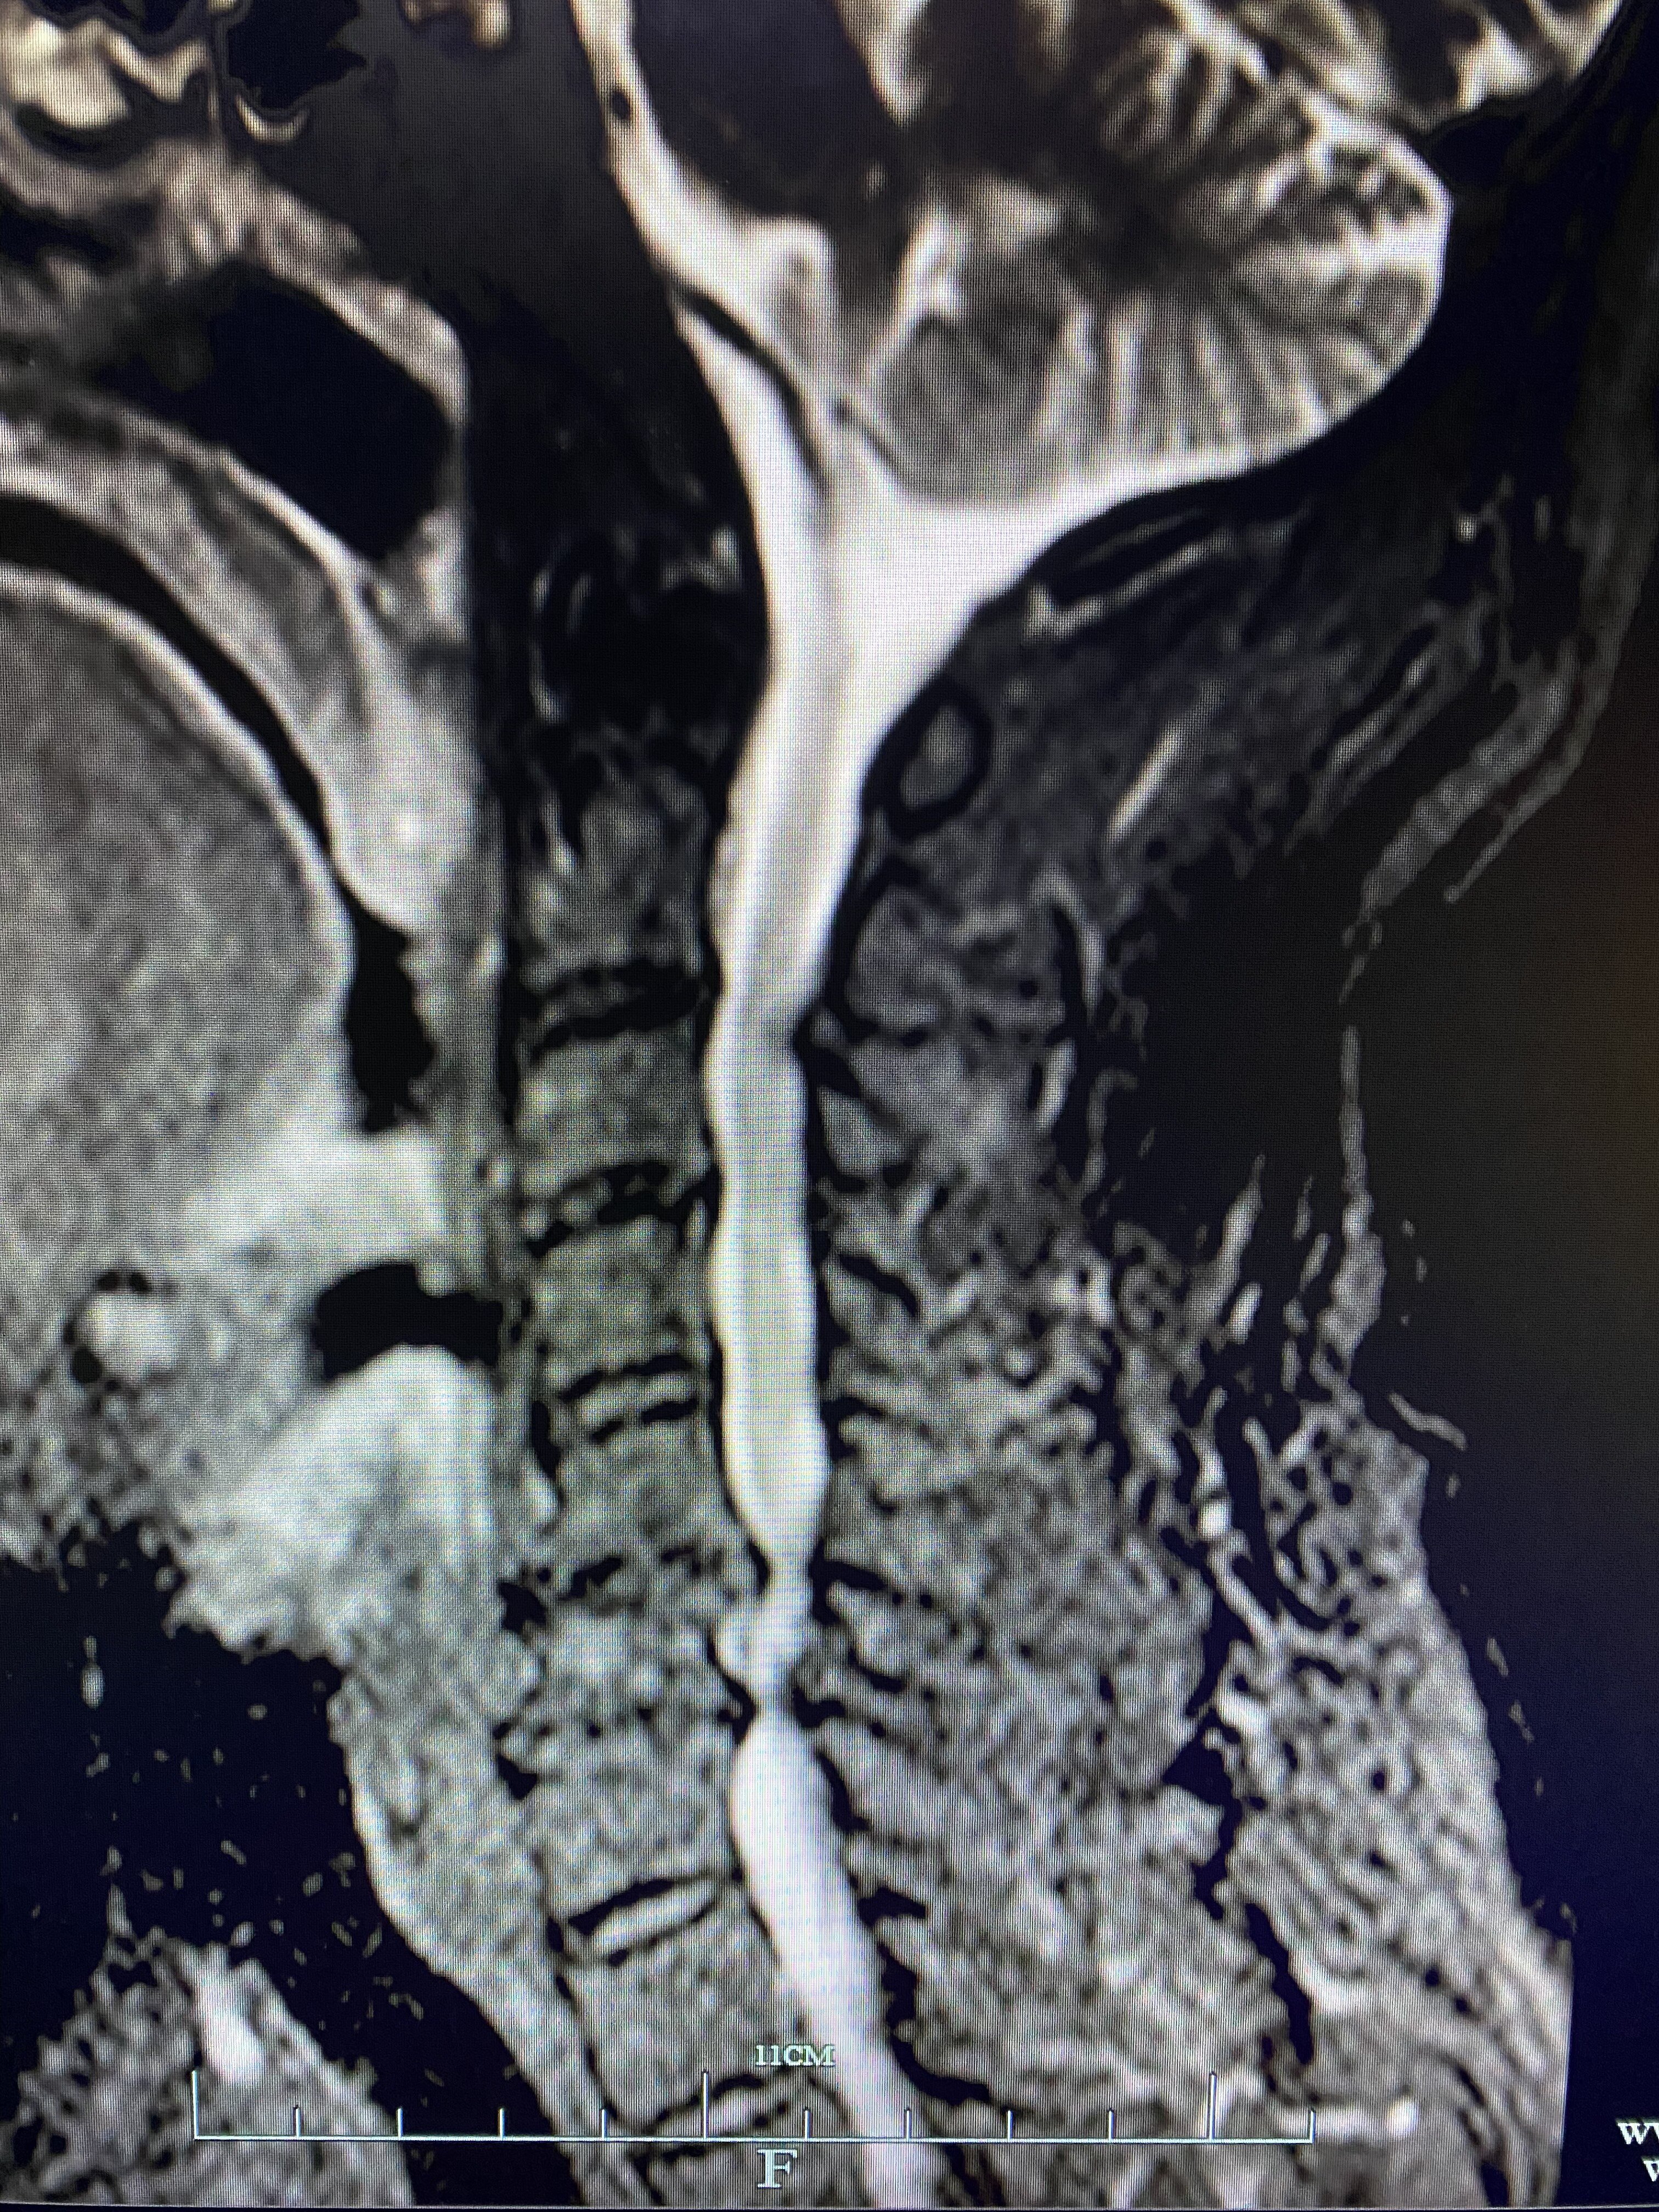

颈椎磁共振示:颈5-7层面脊髓受压变细、脊髓变性

颈椎磁共振轴位片示:脊髓及神经受压严重